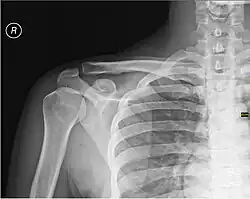

Каркасом плеча служит плечевая кость.

При травмах плеча возможно повреждение нервов и сосудов, а также переломы плечевой кости, наиболее частой локализацией которых является шейка плечевой кости[1].